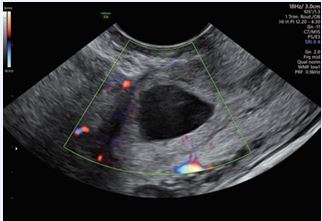

A 29-year-old female presented to our Obstetric Emergency Unit with the main complaint of irregular spotting and vaginal bleeding lasting 7 days. Her medical and surgical history was unremarkable. In her obstetric history, she had undergone a cesarean section at 37 weeks due to fetal distress during induction for an IUGR fetus with trisomy 21. Upon examination, there were no general concerns. At speculum assessment, the cervix appeared normal, with no discharge, and minimal residual uterine bleeding was noted in the vagina. On bimanual examination, the cervix was upward-pointing, the uterus was bulky and anteverted, and the bilateral fornixes were free and non tender. Laboratory tests revealed normal results, with hemoglobin levels within the reference range. A positive β-hCG test indicated a level of 7118 IU/L, which rose to 14,452 IU/L after 48 hours, showing less than a doubling effect. Transvaginal ultrasound performed in the emergency unit showed an empty uterine cavity with clearly defined endometrium. A small, irregular gestational sac-like structure corresponding to five weeks was identified in the lower uterine segment anteriorly, with a vitelline sac and a small embryo without cardiac activity. Both adnexa were normal, and no free fluid was observed in the Douglas pouch. Doppler imaging confirmed the diagnosis of a cesarean scar ectopic pregnancy, revealing excessive vascularity in the hyperechoic rim of the choriodecidual reaction. Ultrasound findings were later corroborated by expert sonographers, with no signs of uterine dehiscence or rupture. Initial management involved monitoring clinical signs and serial β-hCG levels. The patient was asymptomatic, and after thorough counseling regarding pregnancy outcomes (expectant management versus pregnancy interruption), she decided for interruption. Intramuscular Methotrexate was then administered (50 mg/ im). By Day 3, a significant increase in β-hCG levels (22,797 IU/L) and enlargement of the gestational sac (19x17 mm) prompted the decision to administer a single oral dose of 600 mg Mifepristone. Unfortunately, this approach failed to terminate the pregnancy (Figures 1-3). By Day 5, ultrasound imaging confirmed the presence of an embryo with cardiac activity. After additional counseling, the patient consented to a further intervention.

Figure 3: Transvaginal ultrasound - on the previous hysterotomy scar, a single gestational sac is confirmed, measuring 19 × 17 mm, containing a yolk sac and a single embryo with a crown-rump length (CRL) of 2 mm and positive cardiac activity (FHR present).